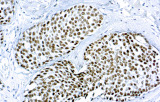

L’immunoistochimica (IHC) con anticorpi primari CE/IVD è essenziale per una diagnosi e classificazione accurata sia delle malignità ginecologiche che mammarie. Questi anticorpi consentono la rilevazione precisa di marcatori tumorali e proteine cellulari, supportando la diagnosi differenziale e guidando strategie terapeutiche personalizzate.

Studi recenti sottolineano il valore diagnostico delle proteine del complesso SWI/SNF, in particolare ARID1B, nell’identificazione di malignità ginecologiche dedifferenziate e indifferenziate – tumori aggressivi con prognosi sfavorevole. L’IHC di ARID1B offre alta specificità e viene sempre più integrata nei pannelli diagnostici per migliorare la precisione. Pannelli con marcatori aggiuntivi supportano anche la differenziazione dei sarcomi uterini, aumentando l’accuratezza diagnostica. Evidenze emergenti suggeriscono che ARID1B potrebbe rappresentare un potenziale bersaglio terapeutico nel carcinoma ovarico a cellule chiare, sebbene le applicazioni cliniche rimangano in fase di ricerca.